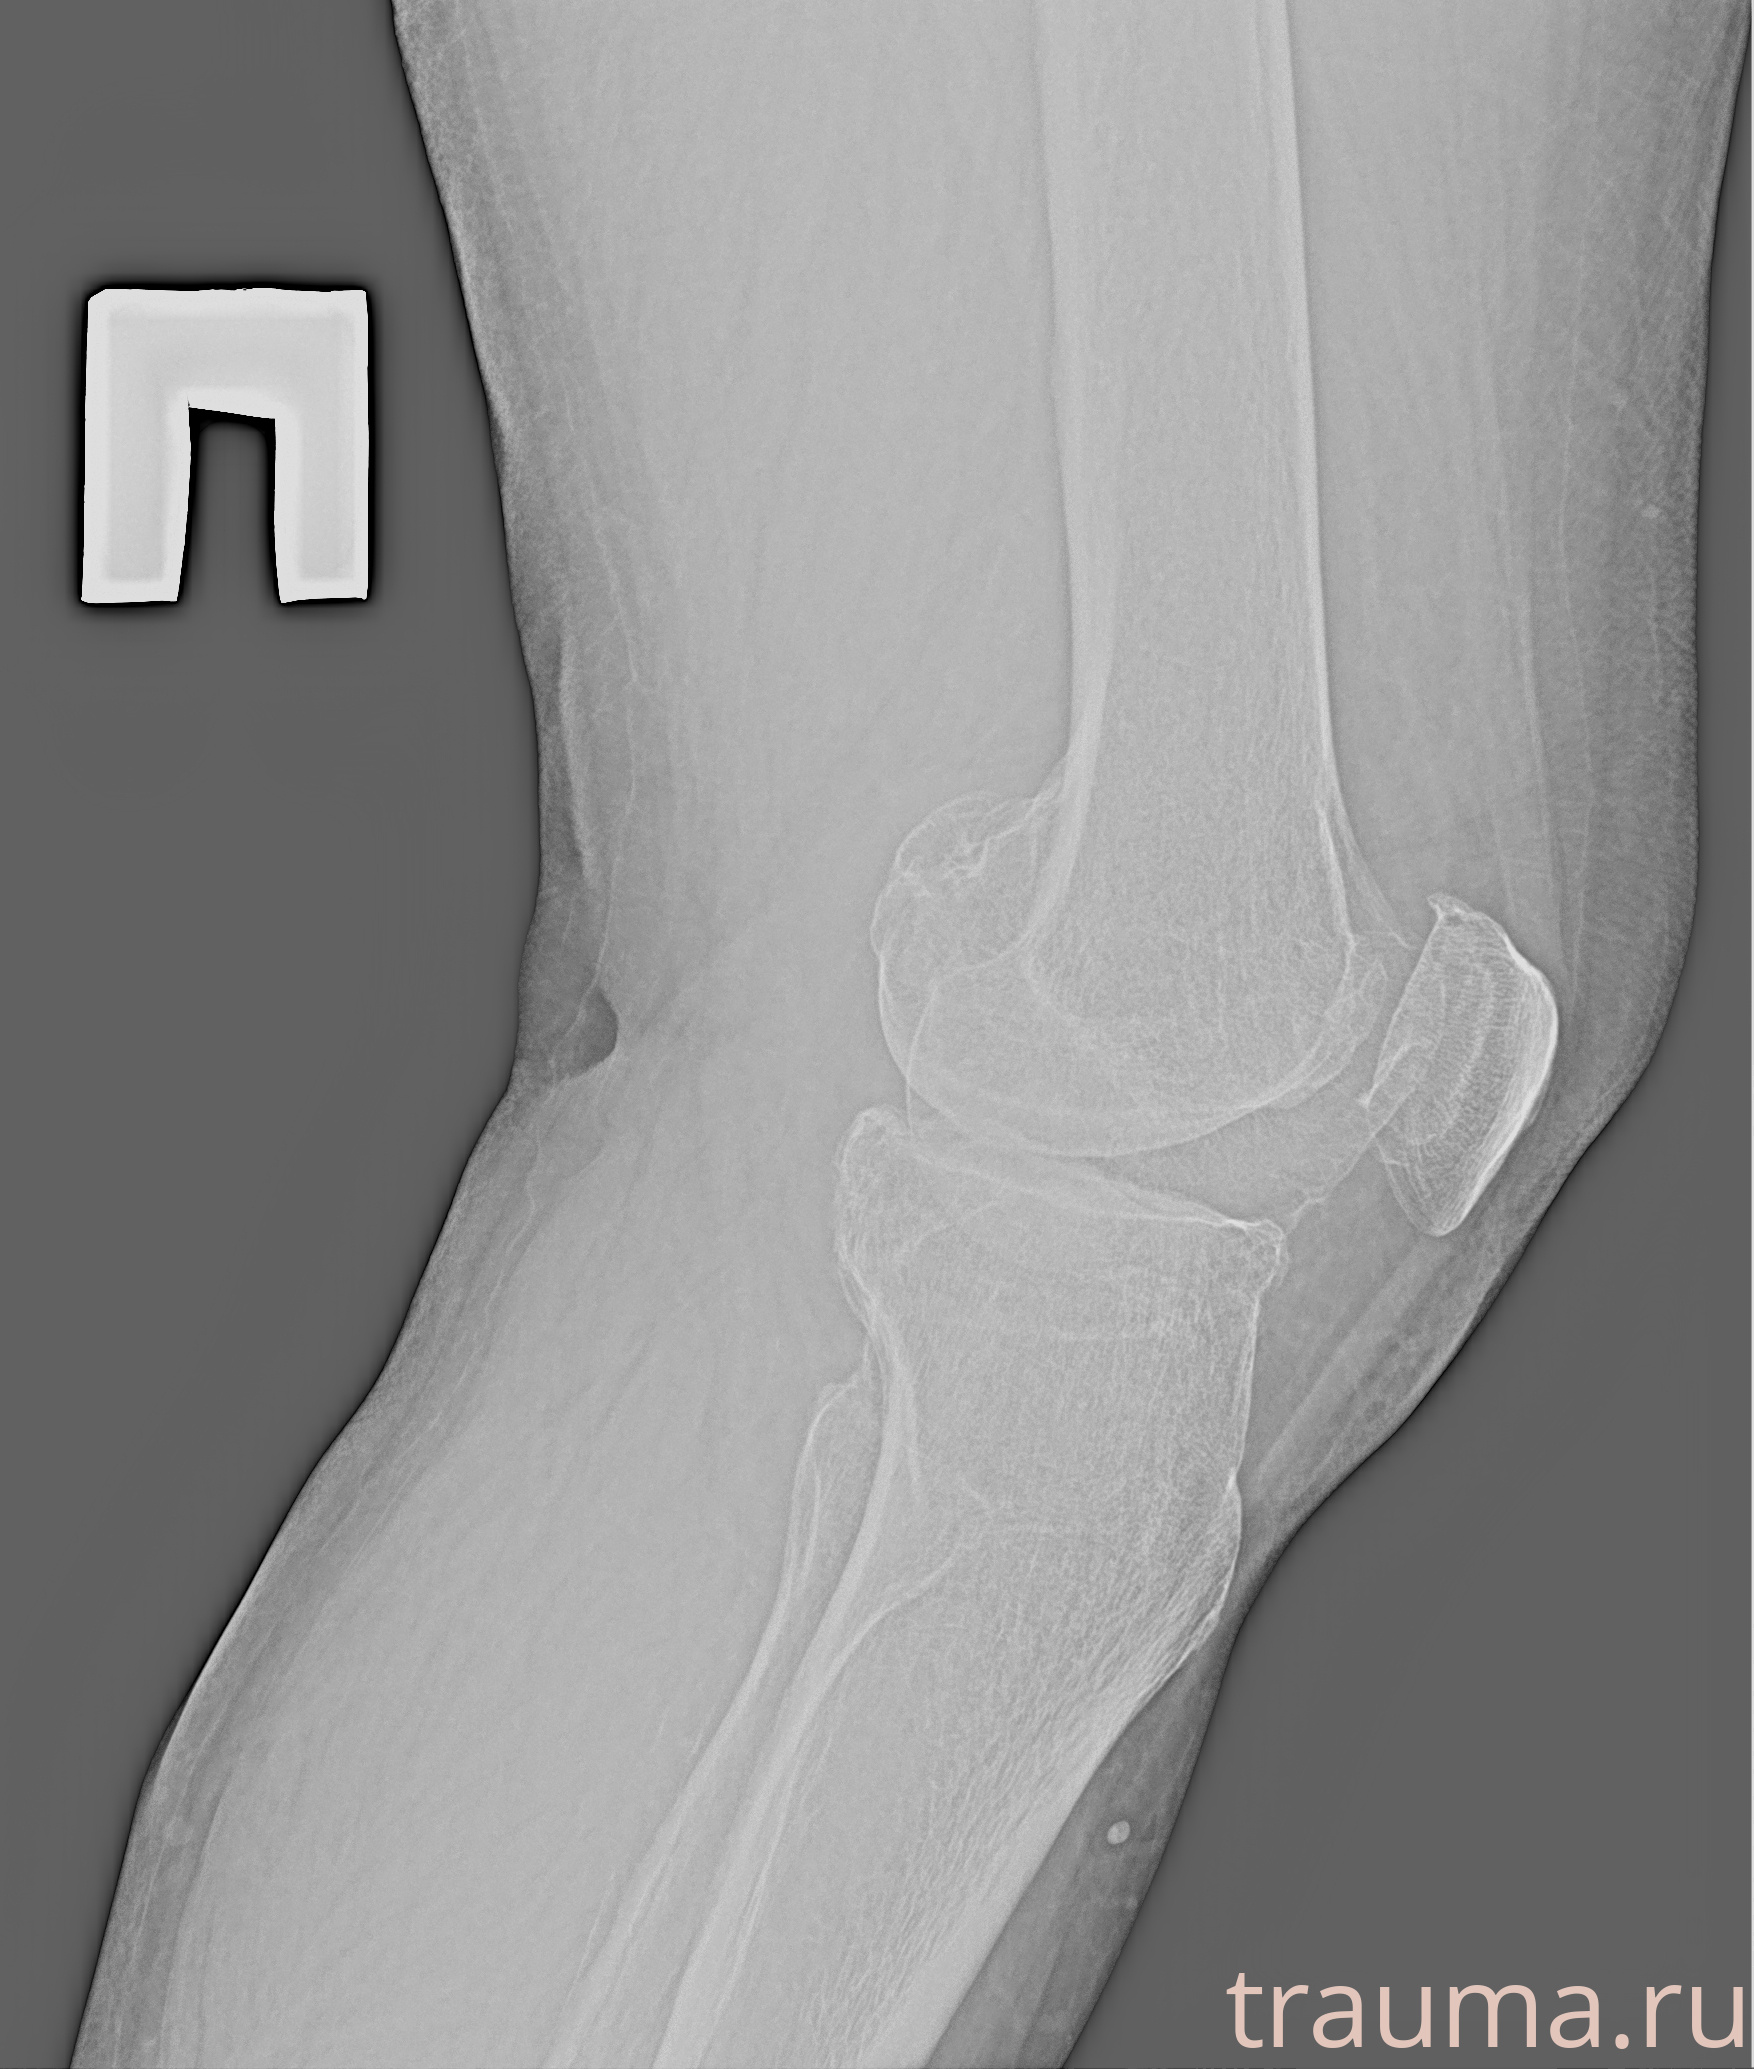

Рентгенограммы

Рентген на дому: по вашему адресу приезжает врач-рентгенолог, травматолог-ортопед с мобильным рентгеновским аппаратом, проводит диагностику травмы или заболевания, делает необходимые рентгенограммы, дает рекомендации по дальнейшему лечению. Получить качественные снимки в домашних условиях возможно благодаря уникальной методике, разработанной МосРентген Центром для института  Склифосовского